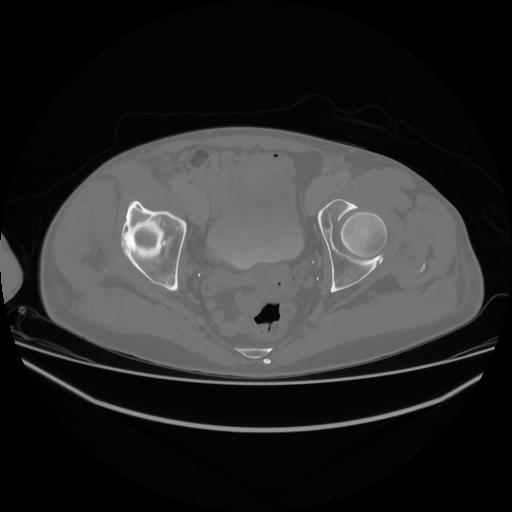

5 CUERPO,CE,Vol,1.0,CUERPO,,